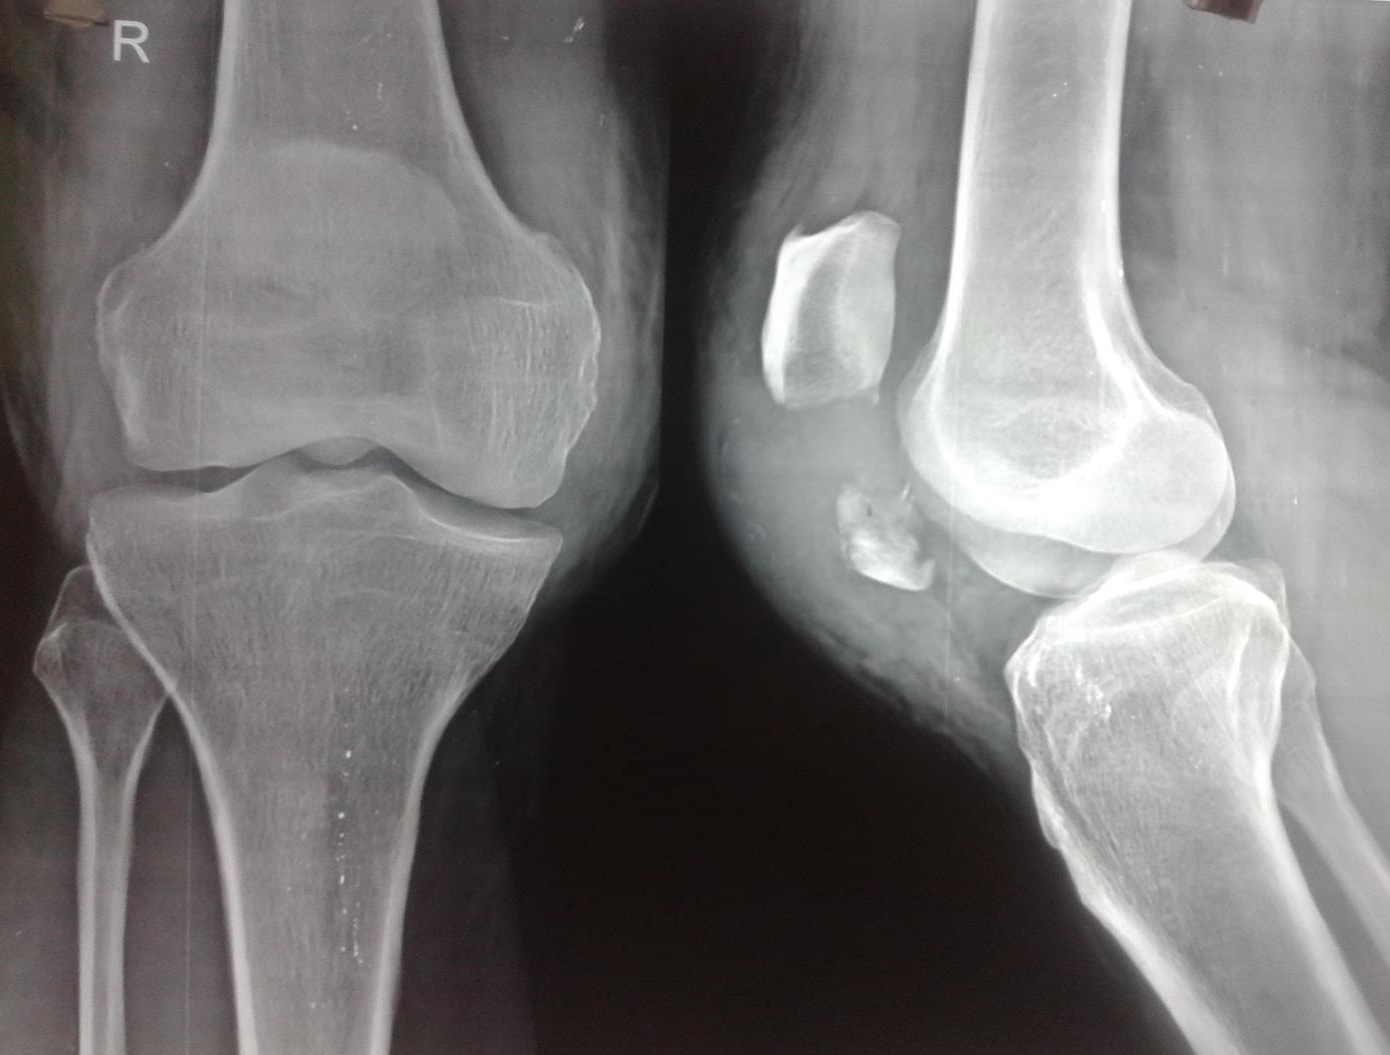

Cureus Vertical Patella Fracture Fixed by Plate and Screws With Bone Broken Knee X-Ray Treatment for a fractured kneecap Patella fractures are traumatic knee injuries caused by direct trauma or rapid contracture of the quadriceps with a flexed knee that can lead to loss of the extensor mechanism. A patella fracture is a break in your kneecap — the small, flat bone that covers and protects your knee joint like a shield. Symptoms of. Broken Knee X-Ray.

Patellar Sleeve Fracture The Western Journal of Emergency Medicine Broken Knee X-Ray The doctor may put mild pressure on the kneecap, and may bend or straighten the leg to see if those actions cause or increase pain or reveal a deformity. Symptoms of a knee fracture include pain, swelling, and bruising at the site of injury; And difficulty bearing weight to walk or stand. A patella fracture is a break in your. Broken Knee X-Ray.